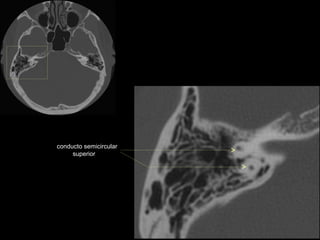

conducto semicircular

superior

conducto semicircular superior